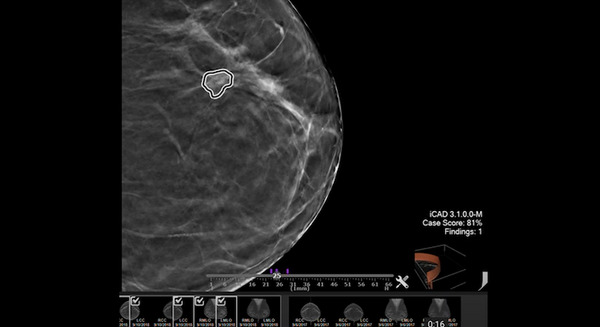

オランダがん研究所 NVIDIA AI Enterpriseで腫瘍の位置を特定できるディープラーニングモデルを構築 2枚目の写真・画像

オランダがん研究所 NVIDIA AI Enterpriseで腫瘍の位置を特定できるディープラーニングモデルを構築